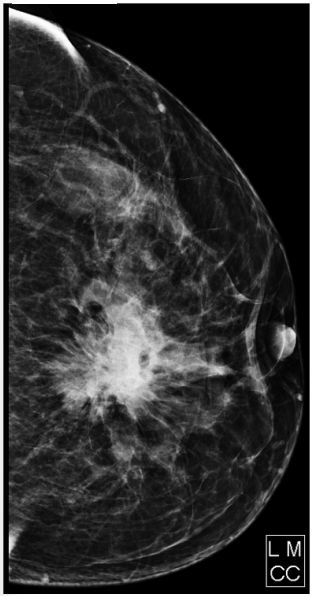

Paciente do sexo feminino, 65 anos de idade, comparece ao serviço para realização de mamografia, queixando-se de massa palpável em mama esquerda e retração de papila. Com relação ao exame abaixo e ao sistema de classificação BI-RADS, assinale a alternativa CORRETA.

Figura 3 – Mamografia.

Enunciado 4478613-1

Fonte: CPCON.